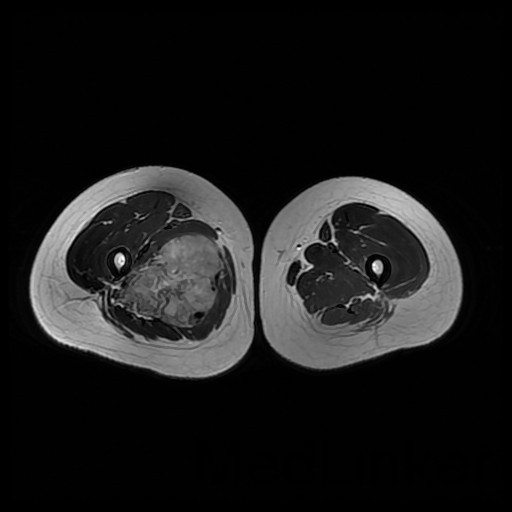

诊断:肺占位性病变(转移瘤?);大腿软组织疾患(右侧大腿肿物) 治疗:入院右下肢MR平扫+增强扫描:右侧大收肌软组织占位性病变,考虑间叶源性恶性肿瘤可能性大,血管源性可能?瘤周多发静脉曲张及侧枝循环形成,建议CT增强扫描进一步检查明确血管情况。遂于声引导下右大腿肿物穿刺活检,病理结果提示:(右大腿肿物)送检穿刺组织,肿瘤细胞形成器官样及腺泡状结构,细胞巢间为纤维性分隔,细胞呈大圆形、多边形,胞质丰富透亮,部分呈嗜伊红色,细胞核大,核分裂象少见,结合临床病史及免疫组化,考虑为腺泡状软组织肉瘤。免疫组化结果(①):CK(-),Vim(-),Ki-67(5%+),HMB45(-),MelanA(-),SMA(+),desmin(-),Myogenin(-),MyoD1(-),S100(-),NSE(部分+),CD56(-)。

1、 腺泡状软组织肉瘤:组织来源不明细胞呈腺泡样或器官样排列的软组织恶性肿瘤,称之为腺泡状软组织肉瘤。 2、好发于青春,女性多见,常位于四肢深部肌肉或筋膜,少数可见于腹壁,肛旁区,舌,腹膜后,颈背部,肿瘤生长缓慢,早期无痛,常偶然发现,大者直径可达6~10cm,瘤块虽增大不快,但血循丰富,浅表者可触及搏动。 3、治疗:原则上应施行肿瘤广泛切除术,边缘切除极易复发,此肿瘤对现行的化疗、放疗不敏感,疗效不肯定,